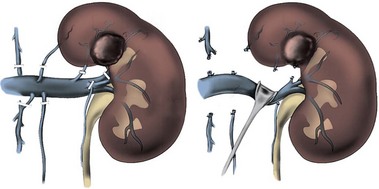

Renal cell carcinoma is associated with venous tumor thrombus in 4% to 10% of cases (Schefft et al, 1978). In the absence of metastases, an aggressive surgical approach with curative intent is justified. Five-year survival rates of 40% to 68% have been reported after radical nephrectomy and tumor thrombectomy (Libertino et al, 1987; Neves and Zincke, 1987; Skinner et al, 1989; Novick et al, 1990b). Although the level of IVC involvement is not predictive of survival, tumor thrombus limited to the renal vein is associated with improved survival compared with thrombus in the IVC (Moinzadeh and Libertino, 2004). The most favorable outcomes are achieved when the tumor does not involve the perinephric fat or regional lymph nodes (Cherrie et al, 1982). Although there are several systems for categorizing venous tumor thrombi based on the distal extent of the thrombus, a rational and commonly employed scheme that is preferred by the senior author is shown in Figure 54–97 and Table 54–12.

Figure 54–97 Classification of venous tumor thrombus extension.

(From Wang GJ, Carpenter JP, Fairman RM, et al. Single-center experience of caval thrombectomy in patients with renal cell carcinoma with tumor thrombus extension into the inferior vena cava. Vasc Endovasc Surg 2008;42[4]:335–40.)

Table 54–12 Classification of Venous Tumor Thrombus Extension

| LEVEL | DISTAL EXTENT OF THROMBUS |

|---|---|

| I | Limited to renal vein |

| II | Infrahepatic inferior vena cava |

| III | Retrohepatic inferior vena cava in proximity to renal veins |

| IV | Supradiaphragmatic inferior vena cava or right atrium |